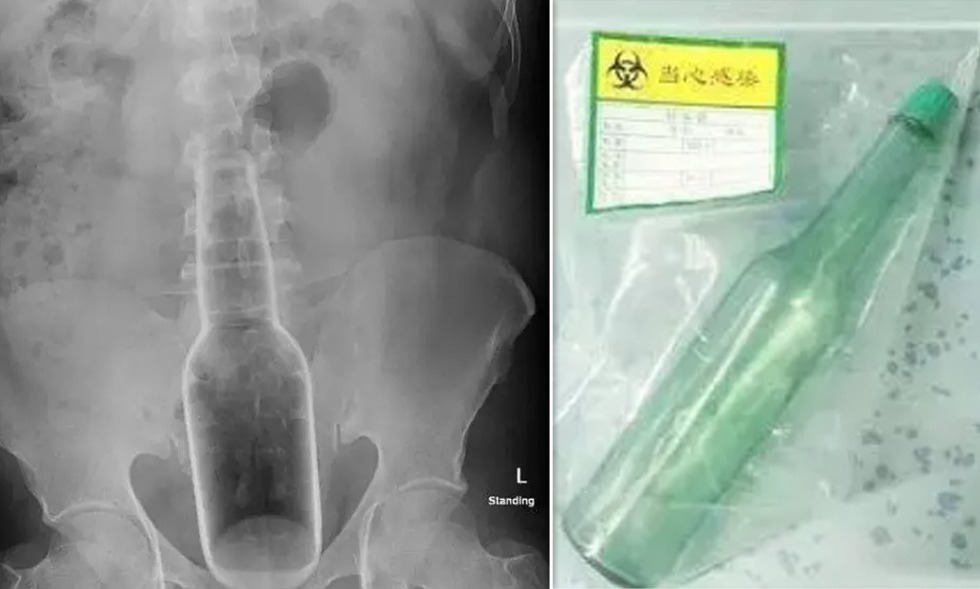

Radiography of a bottle in the rectum